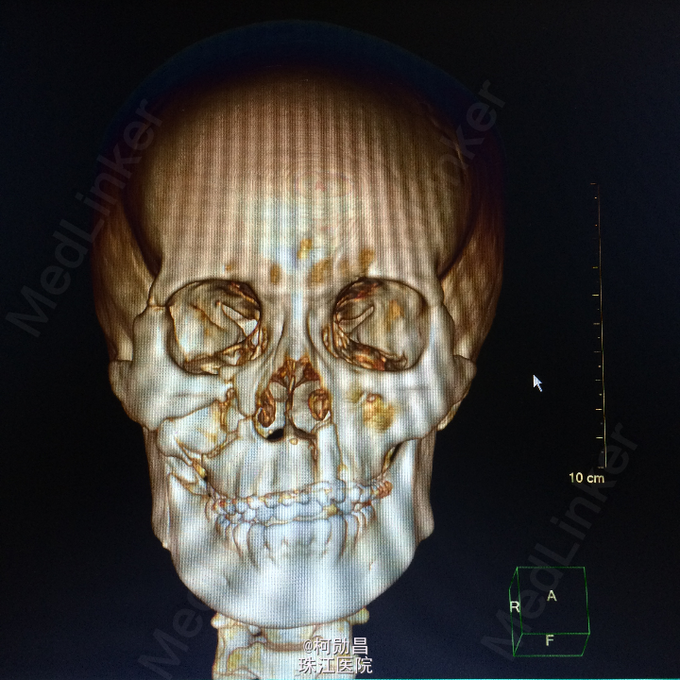

主诉:颅骨损伤后头痛、头晕2天 病史:患者于2天前骑摩托车时与机动车相撞,跌伤头部,至口角、眉弓处多处裂伤出血,左侧外耳道流血,当时患者无意识不清、肢体抽搐等。随即呼叫120送至医院。行头颅CT查示:左顶部硬膜下血肿,蛛网膜下腔出血,予相应治疗后病情稳定 。

查体:脑膜刺激征阳性 辅助检查:复查头颅CT及三维颅骨重建提示:血肿较前吸收,颅骨多发骨折,左额部较为明显

诊断:重型颅脑损伤,脑脊液耳漏、颅骨多发骨折